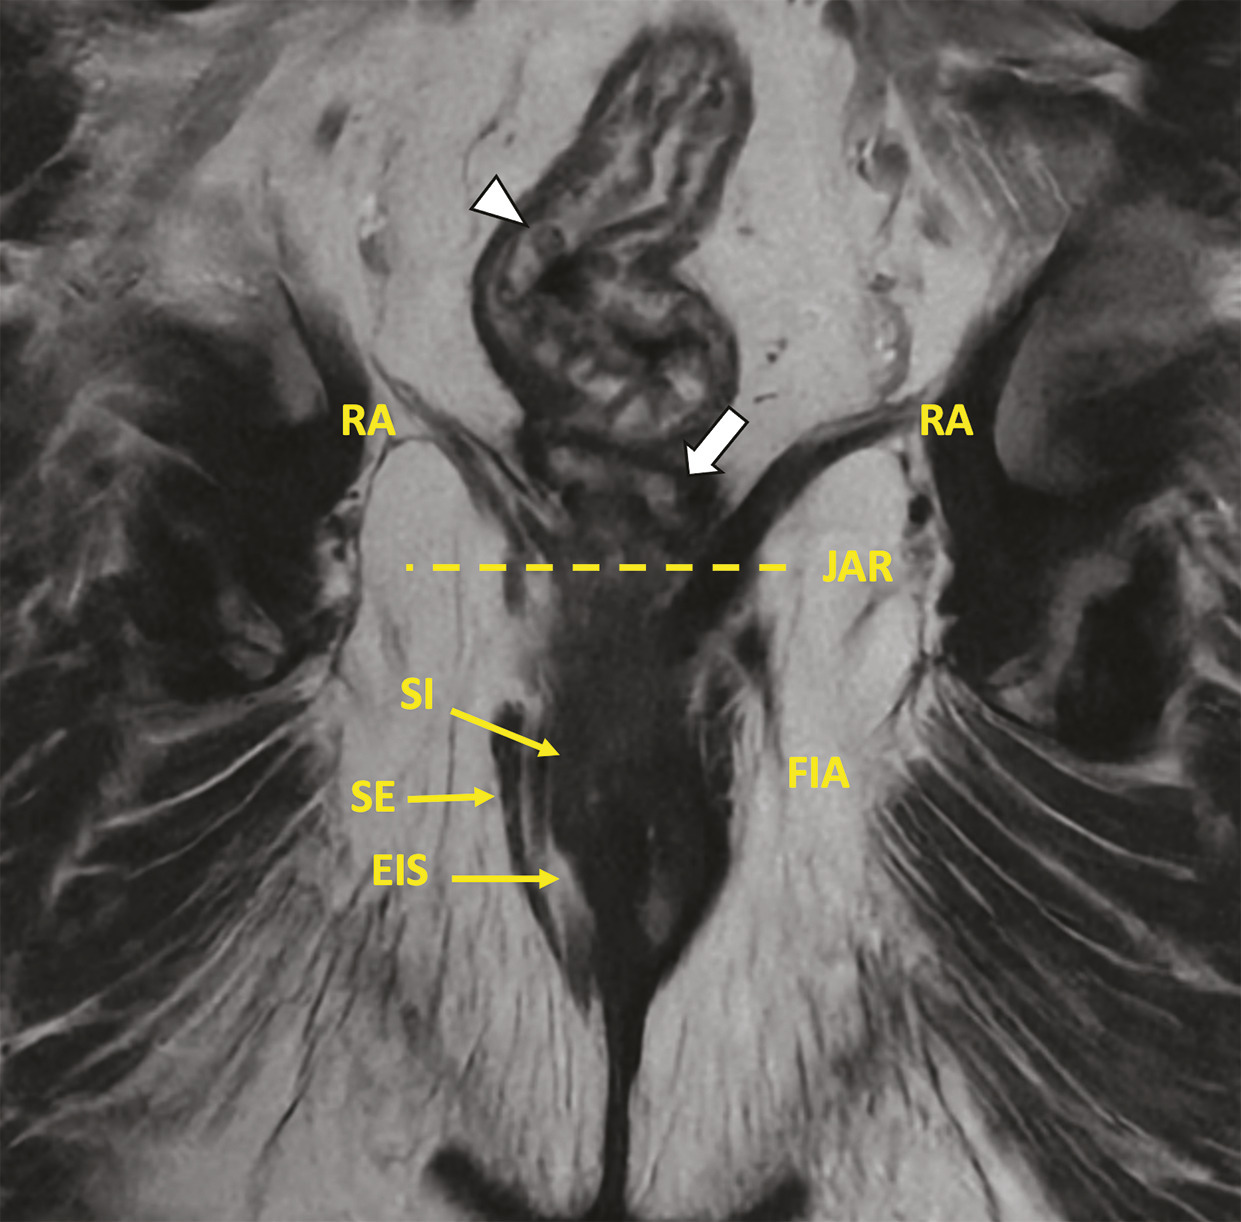

Anatomie anorectale et fistule anale supralévatorienne. IRM en pondération T2, coronale selon l’axe du canal anal montrant un trajet fistuleux en fer à cheval horizontal périrectal bas (flèche). Noter la rectite basse avec épaississement pariétal en rapport avec un œdème sous-muqueux (tête de flèche).